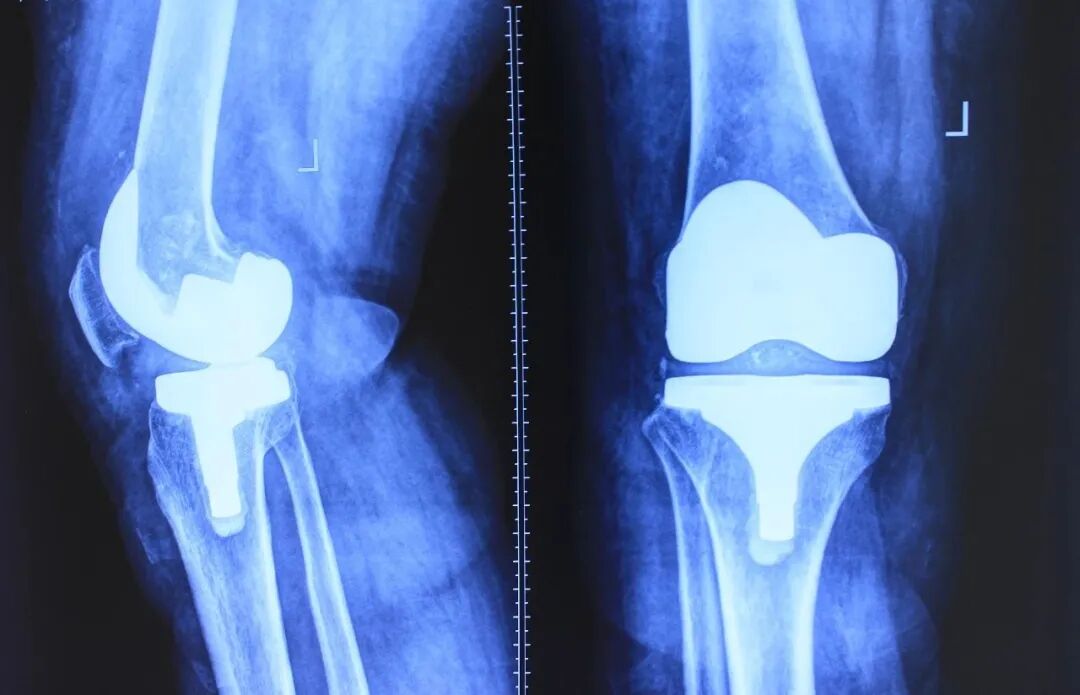

全膝关节置换术目的

缓解膝关节疼痛

纠正膝关节畸形

改善膝关节功能

膝关节置换,并不可怕

膝关节置换术可以有效解决患者关节疼痛、功能障碍、跛行等症状,使患者很快投入到日常生活和工作中,达到日常活动能够自理。